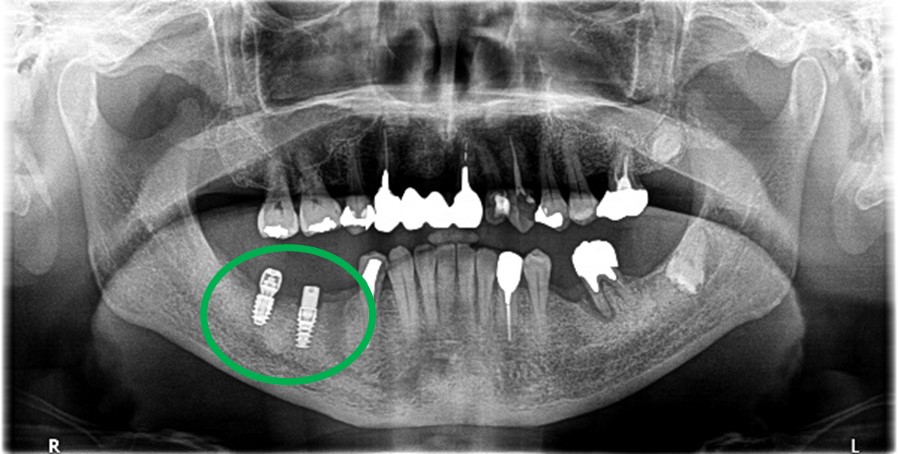

Before

※赤丸を抜歯しました。

After

歯根の周りの骨が全く無い状態でしたので、保存することができず抜歯しました。3本歯がないところに2本インプラントを埋入しました。

所感

抜歯後、歯がなくなったところを補う方法には、部分入れ歯とインプラントがあります。この症例の場合、右下以外ほとんど歯が残っていますので、もし部分入れ歯にした場合、入れ歯のところで他のところと同じ感覚で噛むことができないので、慣れることが大変です。また部分入れ歯の支えになっている歯に負担がかかりますので、今後さらに歯を失う可能性が大きくなります。インプラントは、自分の歯と同じ感覚で噛むことができ、単独で植立していますので他の歯に負担がかかることがありませんので、更に歯を失うことを防ぎます。

インプラント2本:¥363,000×2本=¥726,000(税込)

ポンティック1本:¥115,500(税込)

合計:¥841,500(税込)